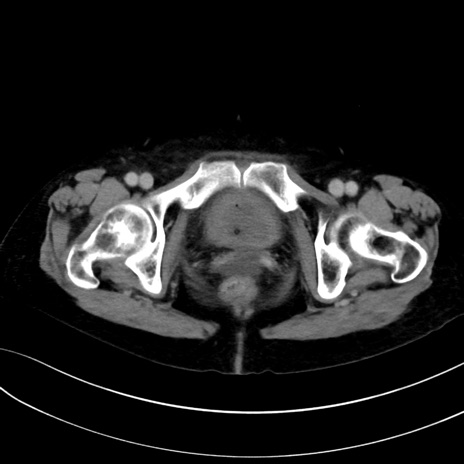

症例13 CT(横断像)1日半後